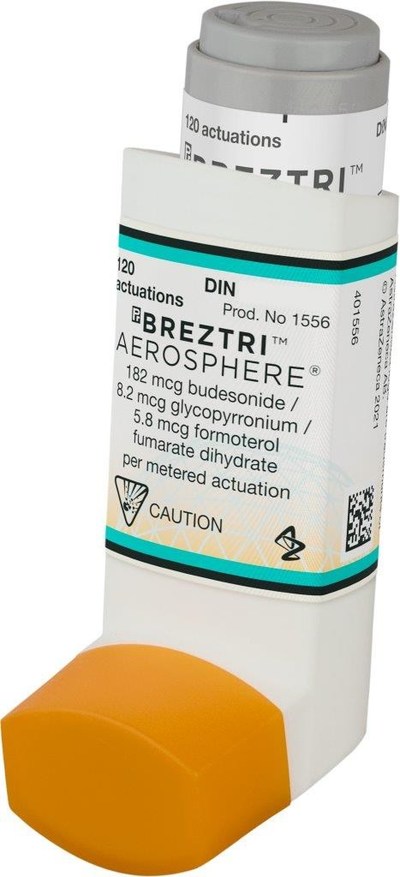

Breztri Aerosphere | Copd, Combination Therapy, Chronic Obstructive

Breztri™ Aerosphere® Now Available In Canada For Long-term Maintenance

Breztri™ Aerosphere® Now Available In Canada For Long-term Maintenance

Breztri™ Aerosphere® Now Available In Canada For Long-term Maintenance